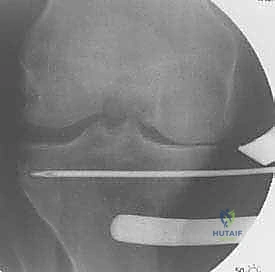

تُعد الأشعة السينية (X-rays) الممتدة من الحوض إلى الكاحل (Scanogram) ضرورية جداً لحساب زاوية التقوس بدقة وتحديد مقدار التعديل المطلوب جراحياً.

قبل العملية، يتم قياس زوايا الركبة بدقة متناهية. كل درجة من درجات التعديل يتم حسابها مسبقاً.

استخدام التخطيط الرقمي يضمن عدم حدوث تصحيح مفرط (Over-correction) أو تصحيح ناقص (Under-correction)، وهو ما يميز الجراح الخبير عن غيره.